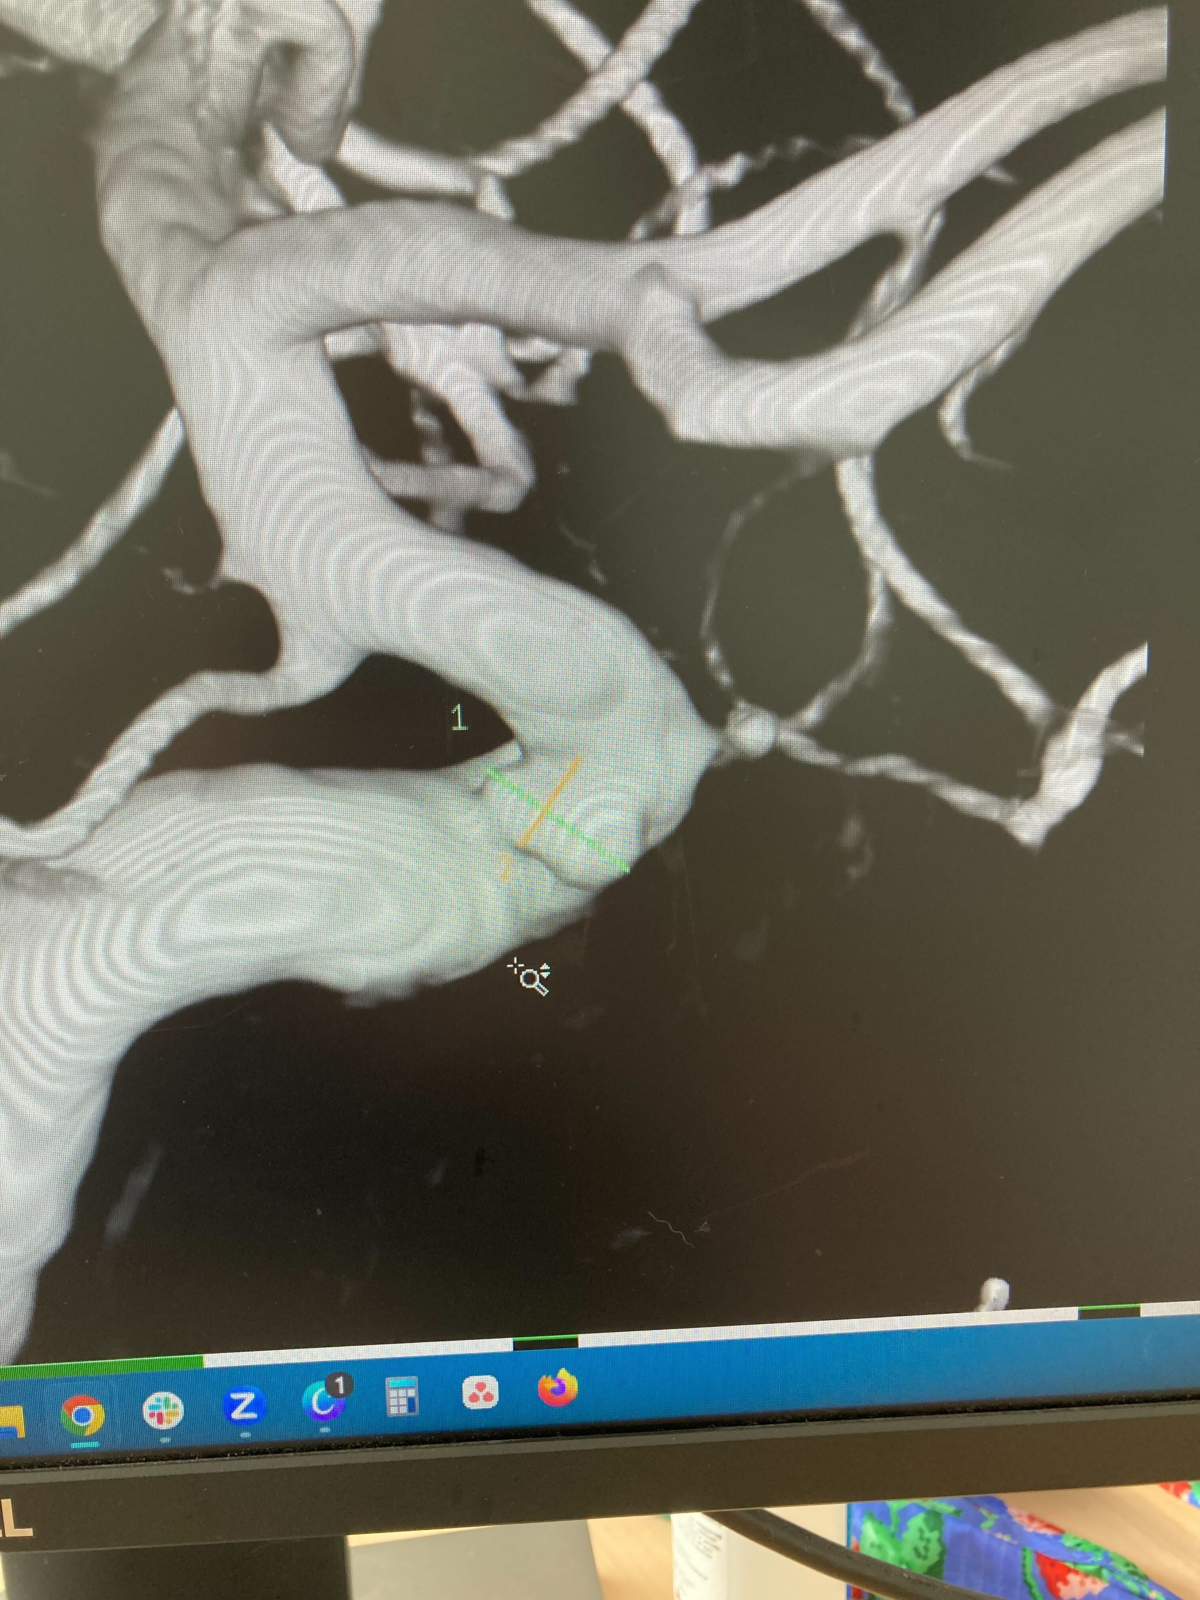

A week later, my husband and I were sitting in the On the Border restaurant in the Orlando airport, on our way to a short vacation. I received a MyChart message, saying my test results from the MR-A were ready to review. There, I found out that I had a 2mm outpouching in the left internal carotid artery, in the opthalmic region of my brain, with the impression stating that it was likely a ‘carotid cave aneurysm’. The neurologist included a quick note – “There is very small, 2 mm brain aneurysm in the left internal carotid artery. No worse at this time but we need to have periodic follow-up scans. No smoking, or heavy drinking. I would like you to see an vascular neurosurgeon, just to establish care, as I do not believe you to have any intervention.” I closed my phone, looked at my husband, and said ‘I have a brain aneurysm’.

The next few weeks were a blur – blood tests, meeting with my neurosurgeon, having an angiogram done which confirmed the aneurysm and increased the size: 4-5mm brain aneurysm. I’m beyond grateful for my neurosurgeon, as he set me up with the best treatment plan (at the time): flow diverter to help blood bypass the aneurysm and heal the aneurysm completely. My surgery was done endovascularly through my wrist, and was a success on May 31st. After 1 day in the Neuro ICU, I was home, and I thought everything would be behind me.

My hope was that this unfortunate story was over at that point, but the excruciating pain returned in late August. I was in the emergency room 5 days in a row and was labeled as drug seeking, and sent home with nothing but Tylenol and a heating pad. Finally, on the 6th visit, I was admitted for pain management and more scans/blood work, and the final decision was to surgically remove my left ovary. During surgery, it was found that my left ovary and fallopian tube had to be removed, rather than just my ovary. This meant a permanent effect on my fertility and lifespan, altering the way that I look at the world. In November 2023, I had my follow up angiogram where my aneurysm was found to be fully treated, and I could stop the Plavix. My nightmare had finally ended.